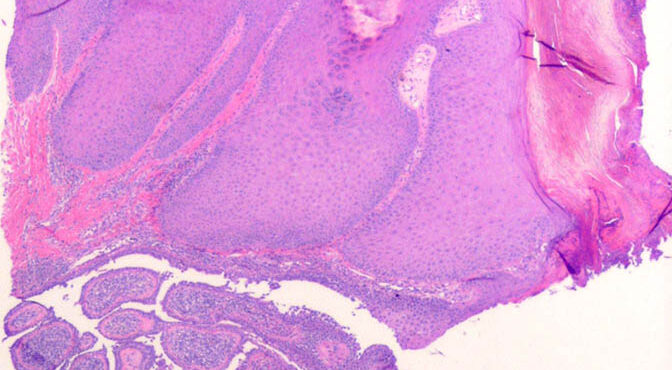

Suture granuloma = الحبيبوم مكان الغرزة الجراحية